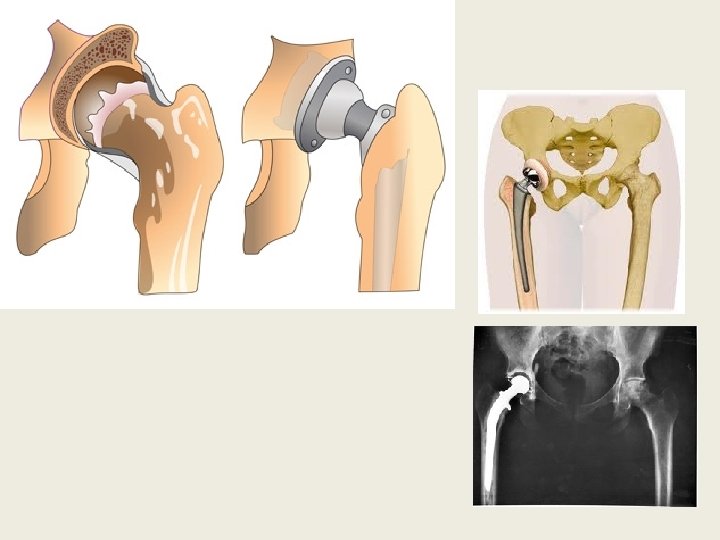

При III степени артроза тазобедренного сустава лечение только хирургическое, с помощью эндопротезирования. Эндопротезирование тазобедренного сустава представляет собой замену поврежденного сустава искусственным протезом. Технически это довольно сложная процедура. Часть протеза вживляется в бедренную кость, часть в таз, как показано на рисунке. Такой протез полностью повторяет характеристики обычного сустава. При I и II степени артроза тазобедренного сустава лечение проводится без хирургического вмешательства. Используются следующие методы: 1. Нестероидные противовоспалительные препараты (индометоцин, пироксикам, кетопрофен, бруфен , диклофенак и др. ) Показаны в период «реактивного воспаления суставов» . Плюсы: Очень хорошо устраняют боли в суставах за счет сильного противовоспалительного действия, снимают отек и само воспаление. Минусы: При длительном использовании препараты данной группы подавляют естественную способность суставного хряща к восстановлению, и побочные эффекты часто негативно влияют на различные внутренние органы. Важно: Не рекомендуется использовать сразу несколько различных противовоспалительных препаратов одновременно. Если используемый препарат недостаточно снимает боль, то следует либо повысить дозу, либо заменить препарат другим. http: //www. koksartroz. ru/lechenie koksartroza tazobedrennogo sustava/ БАДы: Хлорофилл, Босвелия, Омега 3, МСМ.